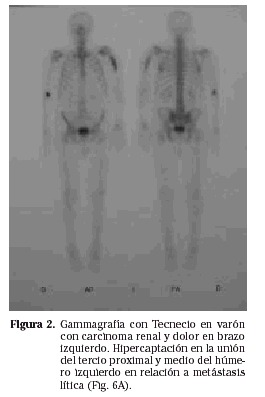

Es un método muy usado y de una gran sensibilidad en la detección de metástasis esqueléticas. Es muy útil en la evaluación de la extensión en la diseminación metastásica. El isótopo más utilizado es el fosfato de Tecnecio 99. El ión fosfato se incorpora en todas las áreas con formación ósea activa, permitiendo la fijación del Tecnecio que puede ser detectado (Fig. 2).